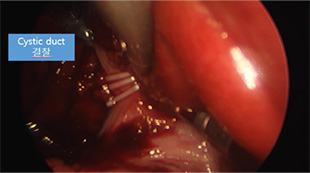

스코프 팁이 상하좌우로 구부러져 장기 뒤쪽까지 시야 확보가 가능하고,